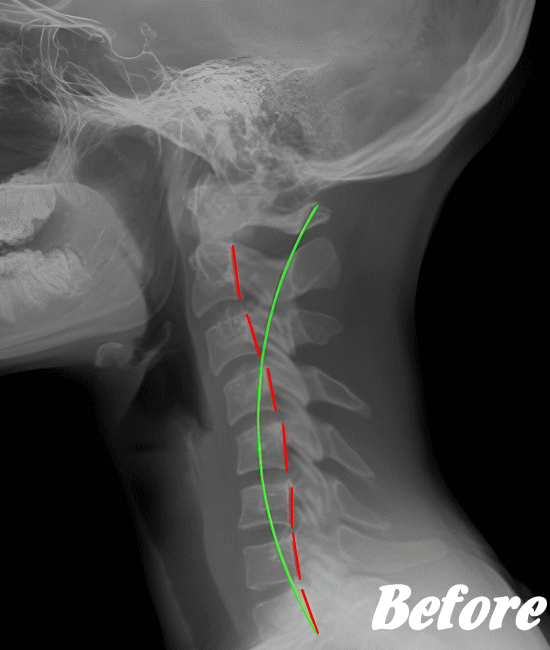

身体に無理をかけず骨や関節の位置を解剖学的に正しい位置へ調整することで、痛みを取り除いていきます。慢性化した痛みも改善します。

多くの場合、頸椎(首の骨)、肩甲骨、背中の胸椎(背骨)、肋骨、そして骨盤(仙腸関節)を調整すれば、痛みは早い段階でなくなり、健康な状態に回復します。